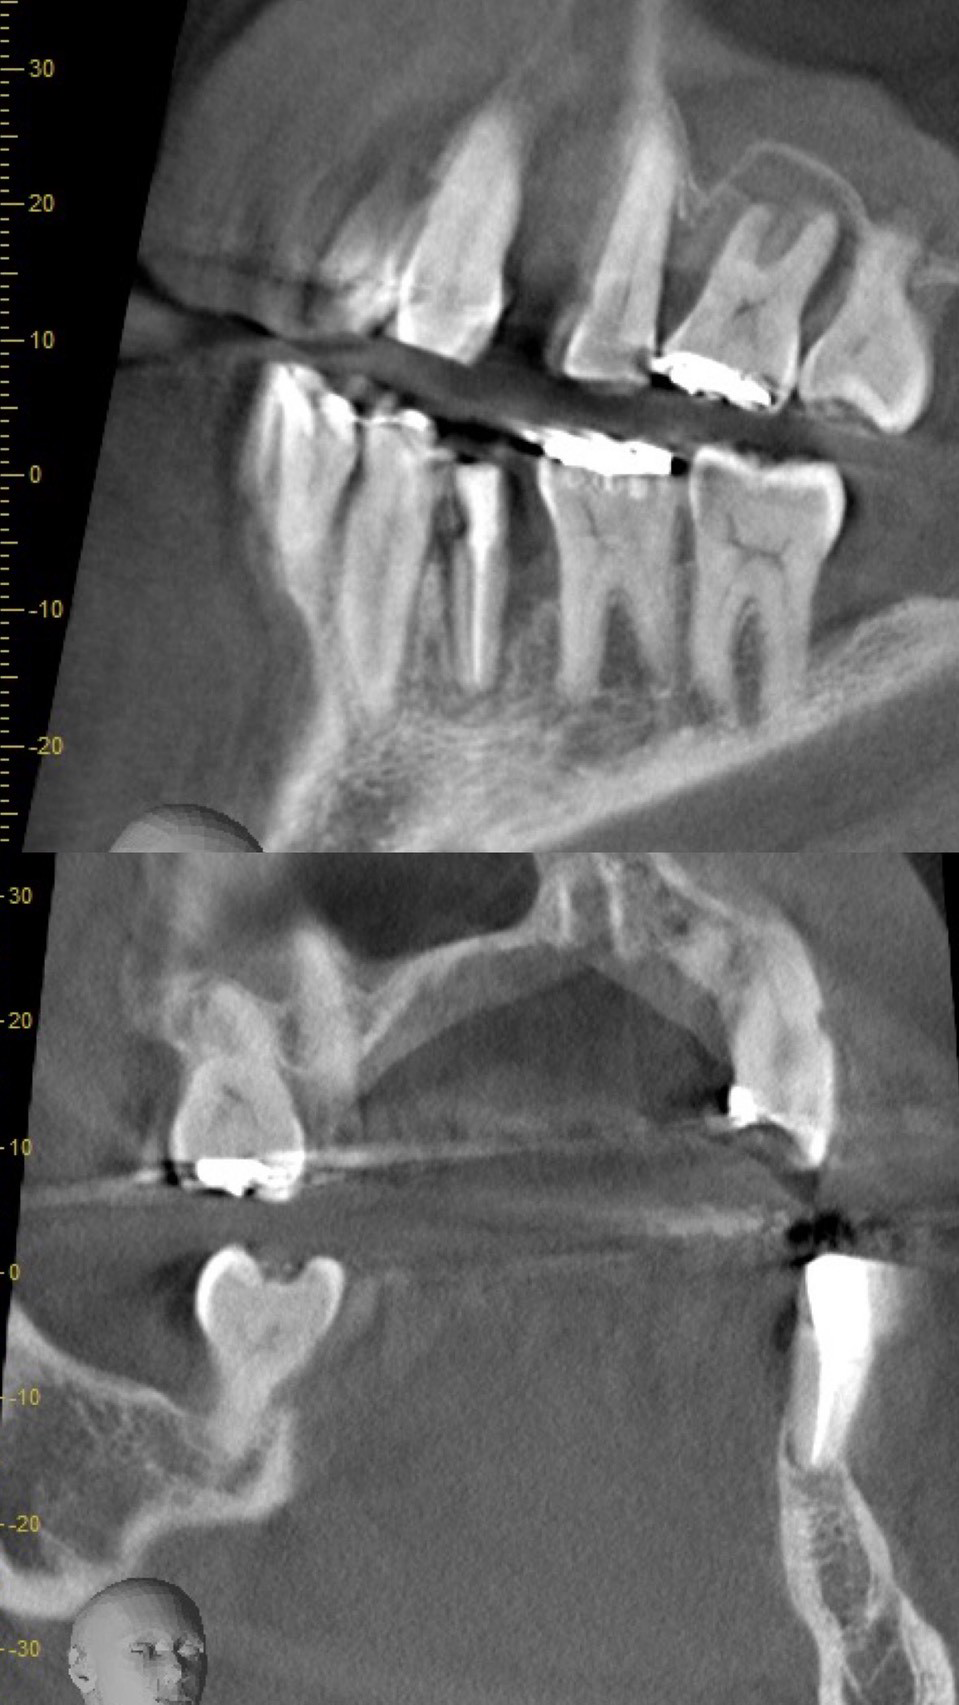

この部分をCTでみてみると、骨の壁がほとんどなくこのままにしておくと、他の歯と同じように自然に抜けてしまう未来が見えます。

先生によっては、抜歯宣告を受けてもおかしくないくらい状態は悪いです。

術前術後のレントゲンでの比較です。明らかに黒く骨欠損が著しかったところが、白く写り良質な骨が復活しているのがわかります。本症例では、骨補填剤は使っていないため全て自家骨での復活です。上顎両側4番目の歯は今後、インプラント治療を行っていく予定です。